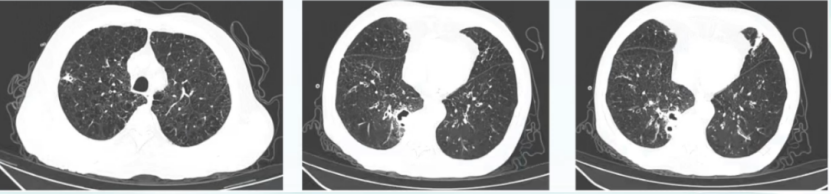

• 胸部CT(2022-08-07):两肺多发结节样高密度影,部分伴空洞,感染性病灶可能,肿瘤性病灶可能,建议进步诊治;两肺多发炎症、渗出;肺气肿,慢性支气管炎;纵隔内多发肿大淋巴结;两侧胸膜增厚(图1)

1  患者胸部CT(2022-08-07)